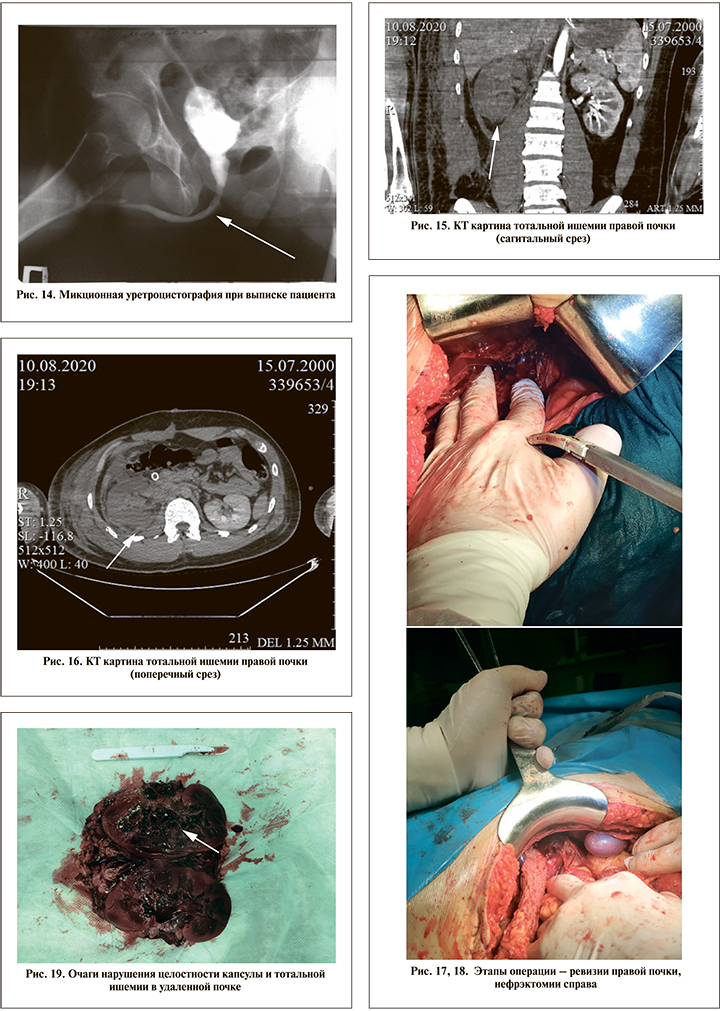

Пострадавший А. 2000 г.р. Автополитравма от 08.08.2020. С места ДТП доставлен в районную больницу, травмоцентр 2-го уровня; в тот же день переведен в ТЦ 1-го уровня, где выполнена лапаротомия, ревизия брюшной полости и забрюшинного пространства. На вторые сутки переведен в госпиталь им. А. А. Вишневского. При обследовании установлен диагноз «сочетанная тяжелая травма головы, груди, живота (ISS – 27 баллов). Открытая черепно-мозговая травма. Тупая травма живота, грудной клетки. Разрыв диафрагмы. Ушиб правой поясничной области. Посттравматический отрыв и тромбоз правой почечной артерии, тотальная ишемия (инфаркт) почки».

Результаты КТ брюшной полости с контрастированием – рис. 15, 16. По неотложным показаниям выполнена операция – правосторонняя нефрэктомия (рис. 17, 18). Ушивание диафрагмы.

На разрезе удаленного макропрепарата видны очаги нарушения целостности капсулы и тотальной ишемии (рис. 19).

Тотальная ишемия правой почки. Компрессия устья правой почечной артерии забрюшинной гематомой в воротах почки. КТ-признаки разрыва капсулы правой почки в средней трети по задней поверхности с минимальной подкапсульной гематомой. Следы жидкости в забрюшинном пространстве справа и отек паранефральной клетчатки.